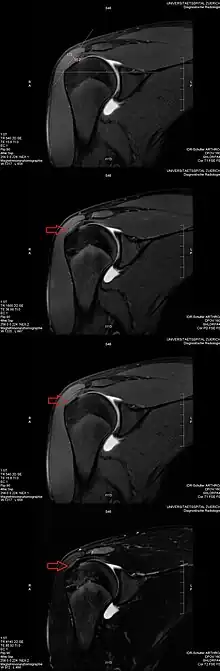

Magic angle effect seen on MRI of the shoulder

The magic angle artifact refers to the increased signal observed when MRI sequences with short echo time (TE) (e.g., T1 or proton density spin-echo sequences) are used to image tissues with well-ordered collagen fibers in one direction (e.g., tendon or articular hyaline cartilage).[1] This artifact occurs when the angle such fibers make with the magnetic field is equal to θm.

Example: This artifact comes into play when evaluating the rotator cuff tendons of the shoulder. The magic angle effect can create the appearance of supraspinatus tendinitis.